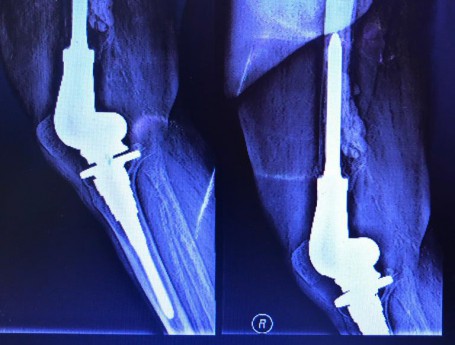

Total Knee Arthroplasty After a non-union